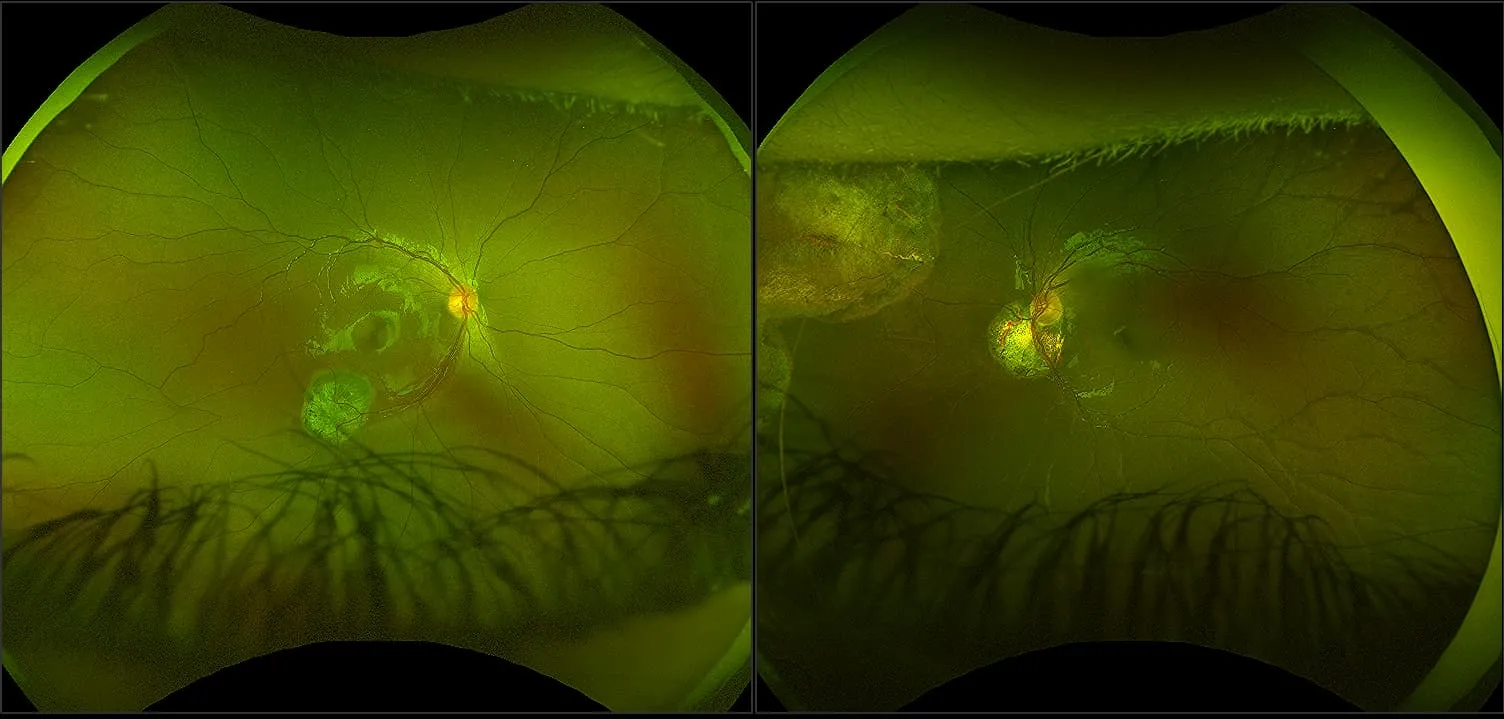

optomap® Recognizing Pathology

This material is designed as a searchable reference resource to support clinical decision-making. The information contained here should be used as general guidance when viewing optomap and OCT images from Optos devices. The differential diagnosis should be made under the direction of the responsible physician. These images were taken on the latest ultra-widefield optomap devices.

The Cases and Images

optomap Recognizing Pathology is searchable by pathology and/or optomap image modality. You may search by multiples of each selection. Each individual case is represented by the accompanying thumbnail image. Most cases include several different optomap image modalities. To view a full description of the case, please click on the thumbnail. Each image in the case will be made available through our OptosAdvance software which provides multi-dimensional visualization of digital images to aid in the analysis of anatomy and pathology. Support and pathology definitions can be found by selecting one of the buttons, above. Should you have questions, please complete the form below.